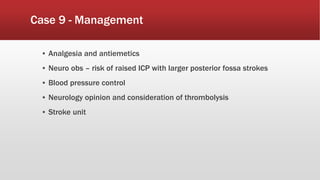

This document discusses various cases of collapse and syncope. It defines collapse as transient loss of consciousness with loss of postural tone and full recovery. Syncope is defined as loss of postural tone with or without loss of consciousness and full recovery. It then discusses the multiple potential causes of collapse and syncope including toxicological, cardiac conduction abnormalities, structural cardiac issues, autonomic dysfunction and more. It then goes through 9 case examples, discussing important questions to ask, potential tests and interventions for each case.